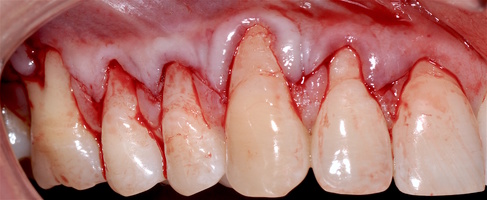

В марте 2017 года в клинику обратилась пациентка Ч., 28 лет (табл. 1) без вредных привычек, с положительным социальным статусом, астенического телосложения. С жалобами на тотальное обнажение корней зубов с повышением чувствительности от термических раздражителей, эстетические дефекты, абразии твердых тканей зубов.

Исходный объем мягкотканного комплекса атрофичен, тонкий биотип десны. Мелкое преддверие полости рта на нижней челюсти в переднем отделе, от 44-го до 34-го зубов высокое прикрепление слизисто-мышечных тяжей.

В области от 1.6 до 2.6 и от 3.6 до 4.6 все зубы имеют некариозные поражения разной степени, такие как эрозии эмали и клиновидные дефекты, вовлекающие в процесс ткани эмали и дентина. Подвижности зубов не выявлено (рис. 1а-е) [9].

При анализе и описании компьютерной конусно-лучевой томографии (рис. 2а-г) была выявлена генерализованная первичная дегисценция вестибулярной пластинки кости от 1/2 до 3/4 длины корней зубов, зубной ряд целостный, все зубы витальны, кариозных поражений нет. Тип кости 1-2 (Lechkolm и Zarb, 1983), первичная дегисценция вестибулярной костной пластинки превышает пределы возрастной атрофии.